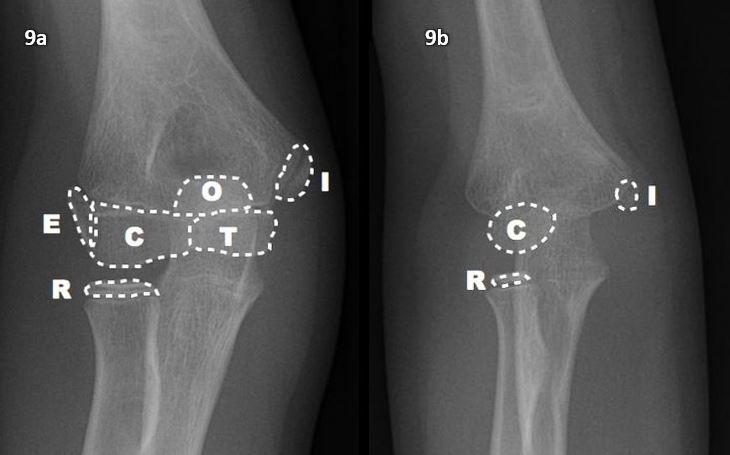

A ordem de aparecimento dos centros de ossificação é constante, sendo usado o mnemônico CRITOE para ajudar na memorização. Já a idade do aparecimento pode variar um pouco, tendendo a ser mais precoce nas meninas em comparação com os meninos. A fusão dos centros de ossificação já pode ser um pouco mais variável, nem sempre seguindo a sua ordem de aparecimento (tabela 1 e figura 9).

Figura 9 (a-b): Radiografias em AP de um adolescente de 14 anos, com todos os centros de ossificação identificados (9a), e de uma criança de 5 anos, idade em que aparecem os centros de ossificação do capítulo e do rádio e já pode começar a aparecer o centro de ossificação do epicôndilo medial. C – capítulo, R – rádio, I – epicôndilo medial, T – tróclea, O – olécrano, E – epicôndilo lateral.